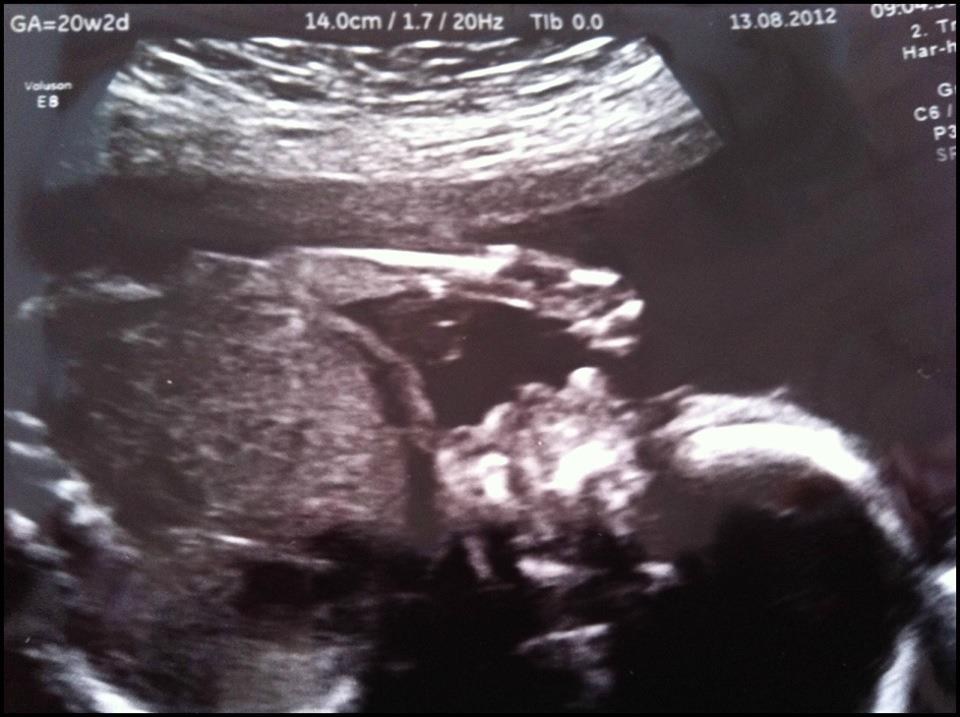

Vi har idag været til MD scanning.

Alle mål på hovede, ben, arme, mave var rigtig fine. Den lille bebsi har nogle flotte lange ben ligesom sin storebror

og det er stadig en skøn lille dreng

Så scannede hun hjertet, der var 4 fine kamre, god tyk skillevæg og flotte hjerteklapper som fungerer perfekt, herefter skulle hun så tjekke blodforsyningen fra hjertet til lungerne, og der begynder den lidt trælse del så

Han har tilsyneladende sin mors næse og hage, og han lå hele tiden og suttede på tommelfinger og åbnede og lukkede munden